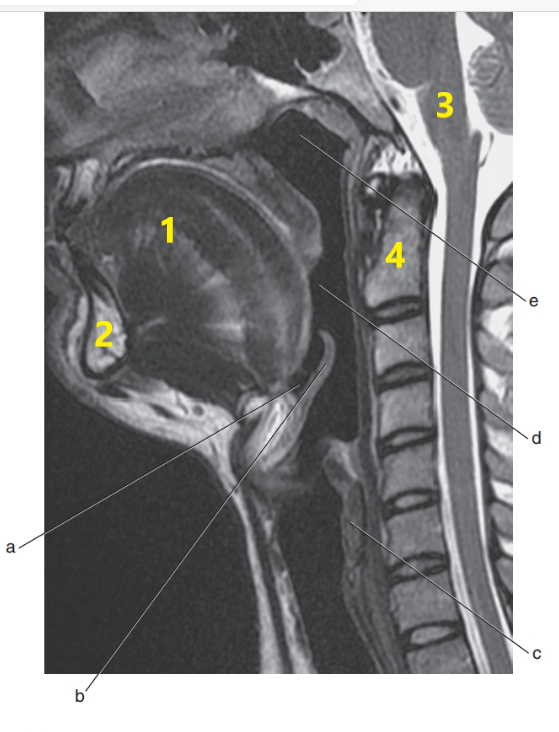

What is h ?

vestibulocochlear nerve

What is g ?

spinal cord

What is 4 ?

C1/C2